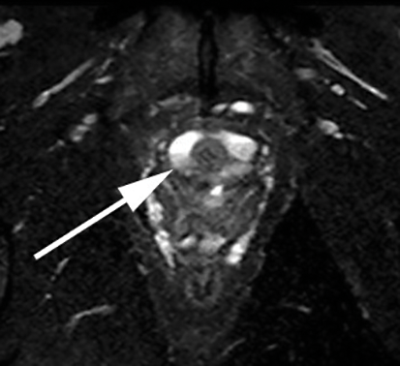

Figure 3d: Coronal T2 SPIR. Images show the saddle diverticulum encasing the urethra.

Uretheral diverticula are usually characterised as a hyperintense periurethral cystic lesion on T2 weighted imaging (Figure 3). They are hypointense on T1 weighted sequences. The diverticula neck may or may not be visualised. The addition of a gadolinium-based contrast agent can help in differentiating diagnoses. Irregular enhancement or mass-like components within a diverticulum may suggest infection or malignancy [2]. Once identified, radiologists should report the size and number of urethral diverticula, as well as the presence of any complications. The position of the diverticular neck if visible should also be commented upon to aid possible surgical intervention [2].